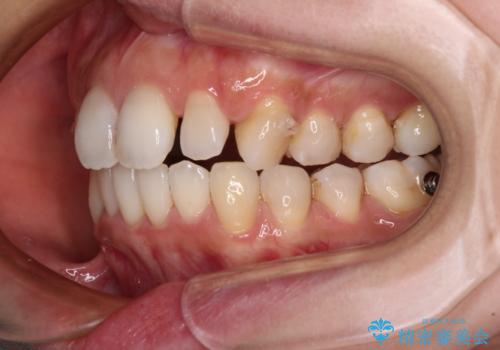

- デコボコと飛び出している前歯を気にして来院された患者様です。

歯列としてはインビザラインでもワイヤー矯正でも対応できるものでしたが、奥歯の咬み合わせを見た時に上顎がやや前方にあり、インビザライン単独では時間のかかってしまう可能性があるため、補助装置を治療当初に使用することで、インビザラインによる治療をスムーズに行えるように計画しました。